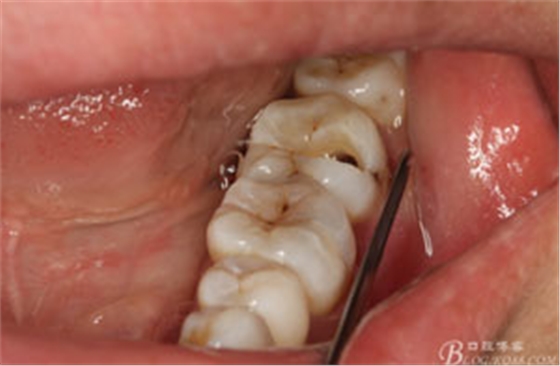

圖2.37牙冠基本完好,松動Ⅰ度。合面有一開髓孔被棉球覆蓋,頰側(cè)牙齦輕度紅腫。

圖3.取出棉球口內(nèi)發(fā)現(xiàn)37合面有開髓孔,探針出血,頰側(cè)牙齦紅腫